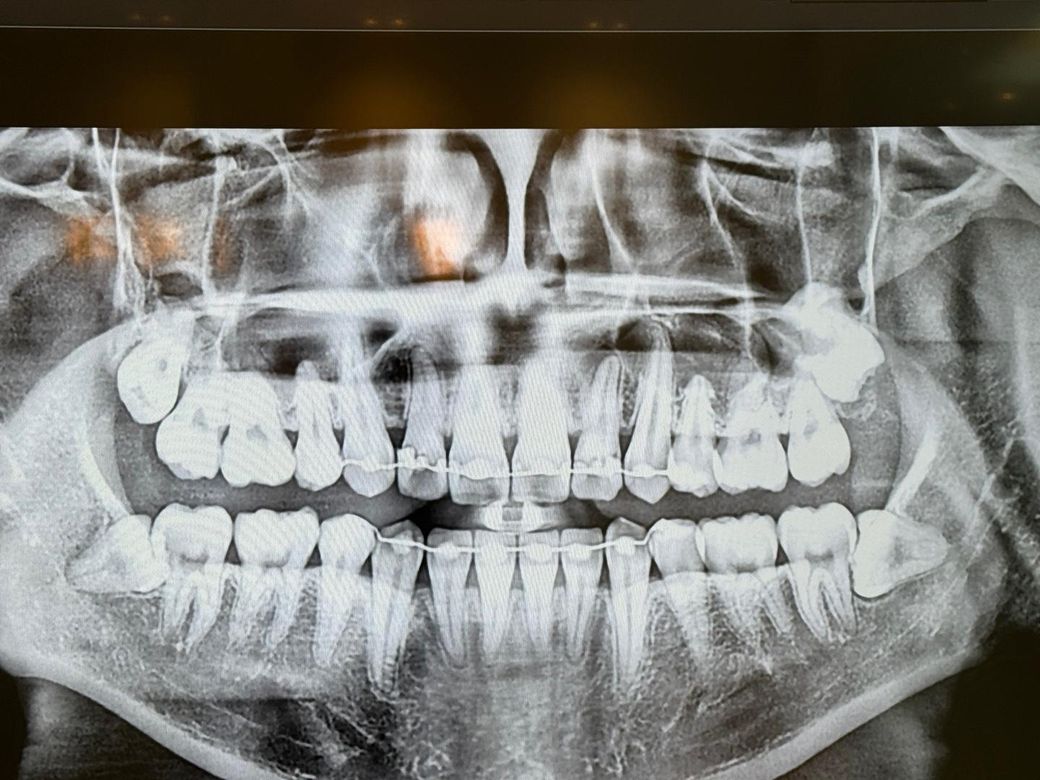

치아 뿌리끝 염증 누공 꼭 신경치료해야할까요

올해 6월달에 찍은 파노라마에서 여기 의사분들이 다 이정도는 괜찮다고 고통도 없어서 일단 지켜보자 하셨는데

11월 2일쯤 이렇게 됐네요 2번째 사진은 오늘 사진

• 1번 째 사진

• 2번 째 사진

• 3번 째 사진